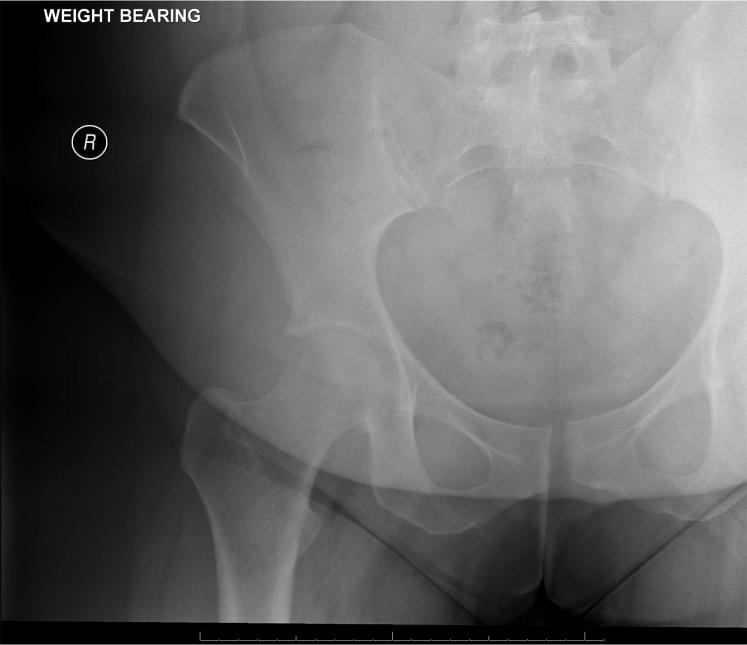

Laparoscopic Treatment of Pubic Symphysis Instability With Anchors and Tape Suture.

Patients with pubic symphysis instability who had failed nonoperative treatments may benefit from surgical repair. This disease process is rare, most commonly seen in postpartum women and athletes, and its surgical treatment is invasive and nonphysiological. Currently described surgical interventions, although limited, include plating, which provides an overly rigid construct with the risk of failure and possibly poor long-term outcomes particularly in athletes, and treatments such as curettage, more commonly used in the treatment of osteitis pubis. An emerging option is minimally invasive laparoscopic fixation using knotless anchors with a tape suture in a crisscross configuration. This possibly allows more physiological movement of the pubic symphysis in a less invasive manner. A detailed technical description and discussion of the technique are provided.

耻骨联合不稳定且非手术治疗失败的患者可能从手术修复中获益。这种疾病过程罕见,最常见于产后女性和运动员,其手术治疗具有侵入性且不符合生理状态。目前描述的手术干预措施虽然有限,但包括钢板固定,这会提供过于刚性的结构,存在失败风险,尤其在运动员中可能导致不良的长期预后,还有诸如刮除术等治疗方法,更常用于耻骨炎的治疗。一种新兴的选择是使用无结锚钉和带缝线以交叉配置进行微创腹腔镜固定。这可能以微创方式使耻骨联合实现更多的生理性活动。本文提供了该技术的详细技术描述和讨论。